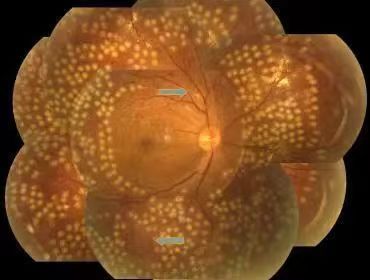

不同程度的糖尿病視網膜病變

視網膜激光光凝:采用激光的熱凝效用,在局部出血部位和(或)無灌注區形成凝固激光斑,達到止血、預防再出血的效果。該治療為增殖期病變的首選治療方式,較早實行全視網膜光凝能有效預防失明,且價格低廉,效果較好。

激光光凝治療

視網膜激光光凝術是治療糖尿病性視網膜病變(DR)的重要手段,分為全視網膜激光光凝(PRP)、黃斑格柵樣激光光凝等。激光光凝術是高危增殖性糖尿病性視網膜病變(DR)患者及某些嚴重非增殖性患者的主要治療方式。

激光治療旨在減少視力進一步下降的危險,盡量保護視功能。高危增殖性糖尿病性視網膜病變患者應迅速施行全視網膜激光光凝治療。約50%的重度非增殖性糖尿病性視網膜病變患者在1年內可進展為增殖性糖尿病性視網膜病,15%進展為高危增殖性糖尿病性視網膜病,若病情進展應考慮行全視網膜激光光凝治療。

全視網膜激光光凝術后